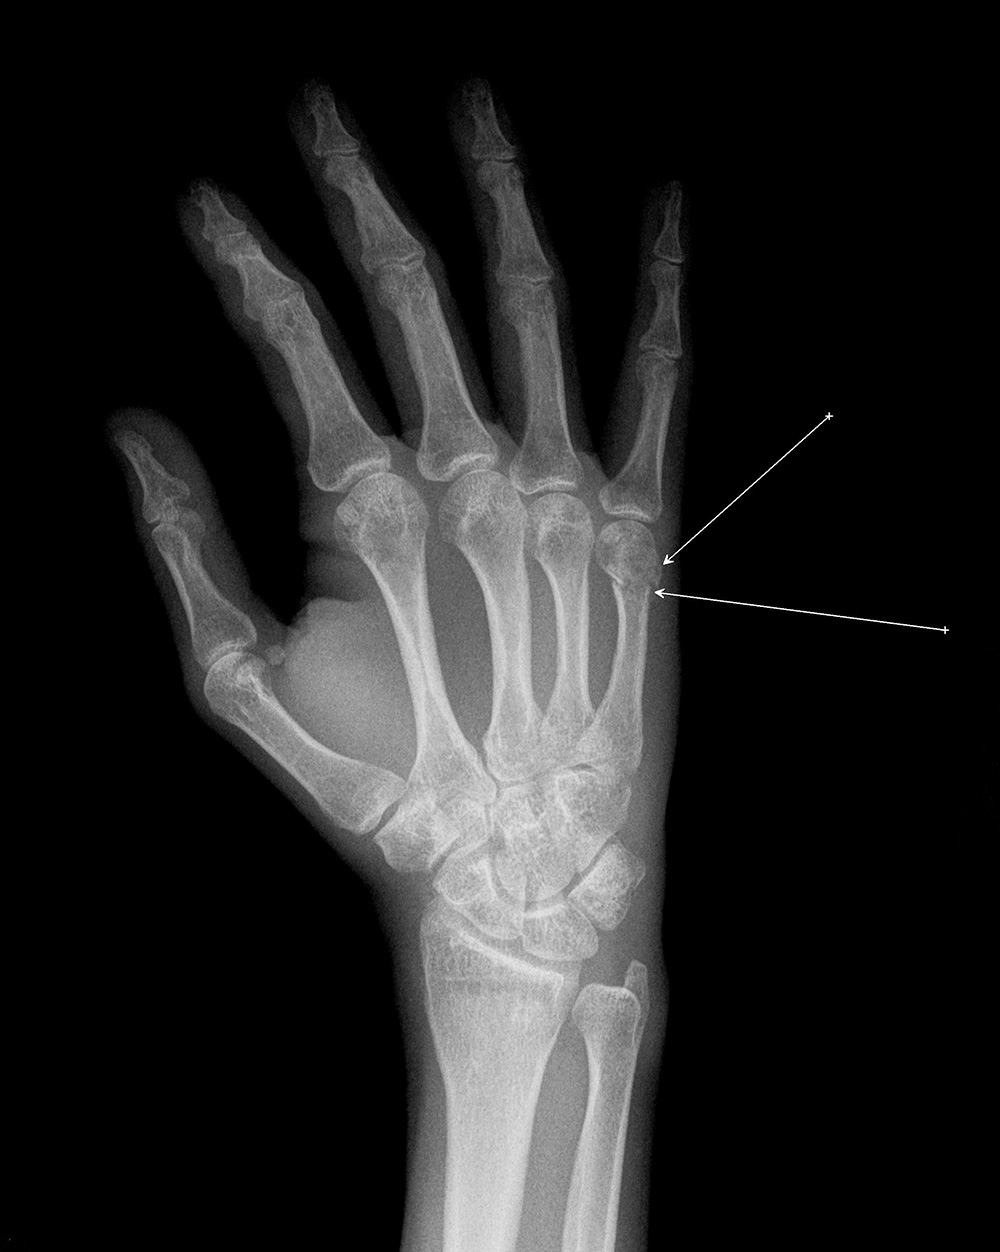

На рентгенограмме левой кисти в 2-х проекциях - околосуставной остеопороз с участками кистозной перестройки, в области дистального метафиза 5-ой пястной кости имеется не полностью сопоставленный, слабо консолидированный перелом, лучезапястный сустав - межсуставная щель сохранена, суставные поверхности с ровными контурами, умеренный субхондральный остеосклероз.

5. Рентгенография кисти- в области метафиза 5-ой пястной кости имеется перелом со смещением костных отломков